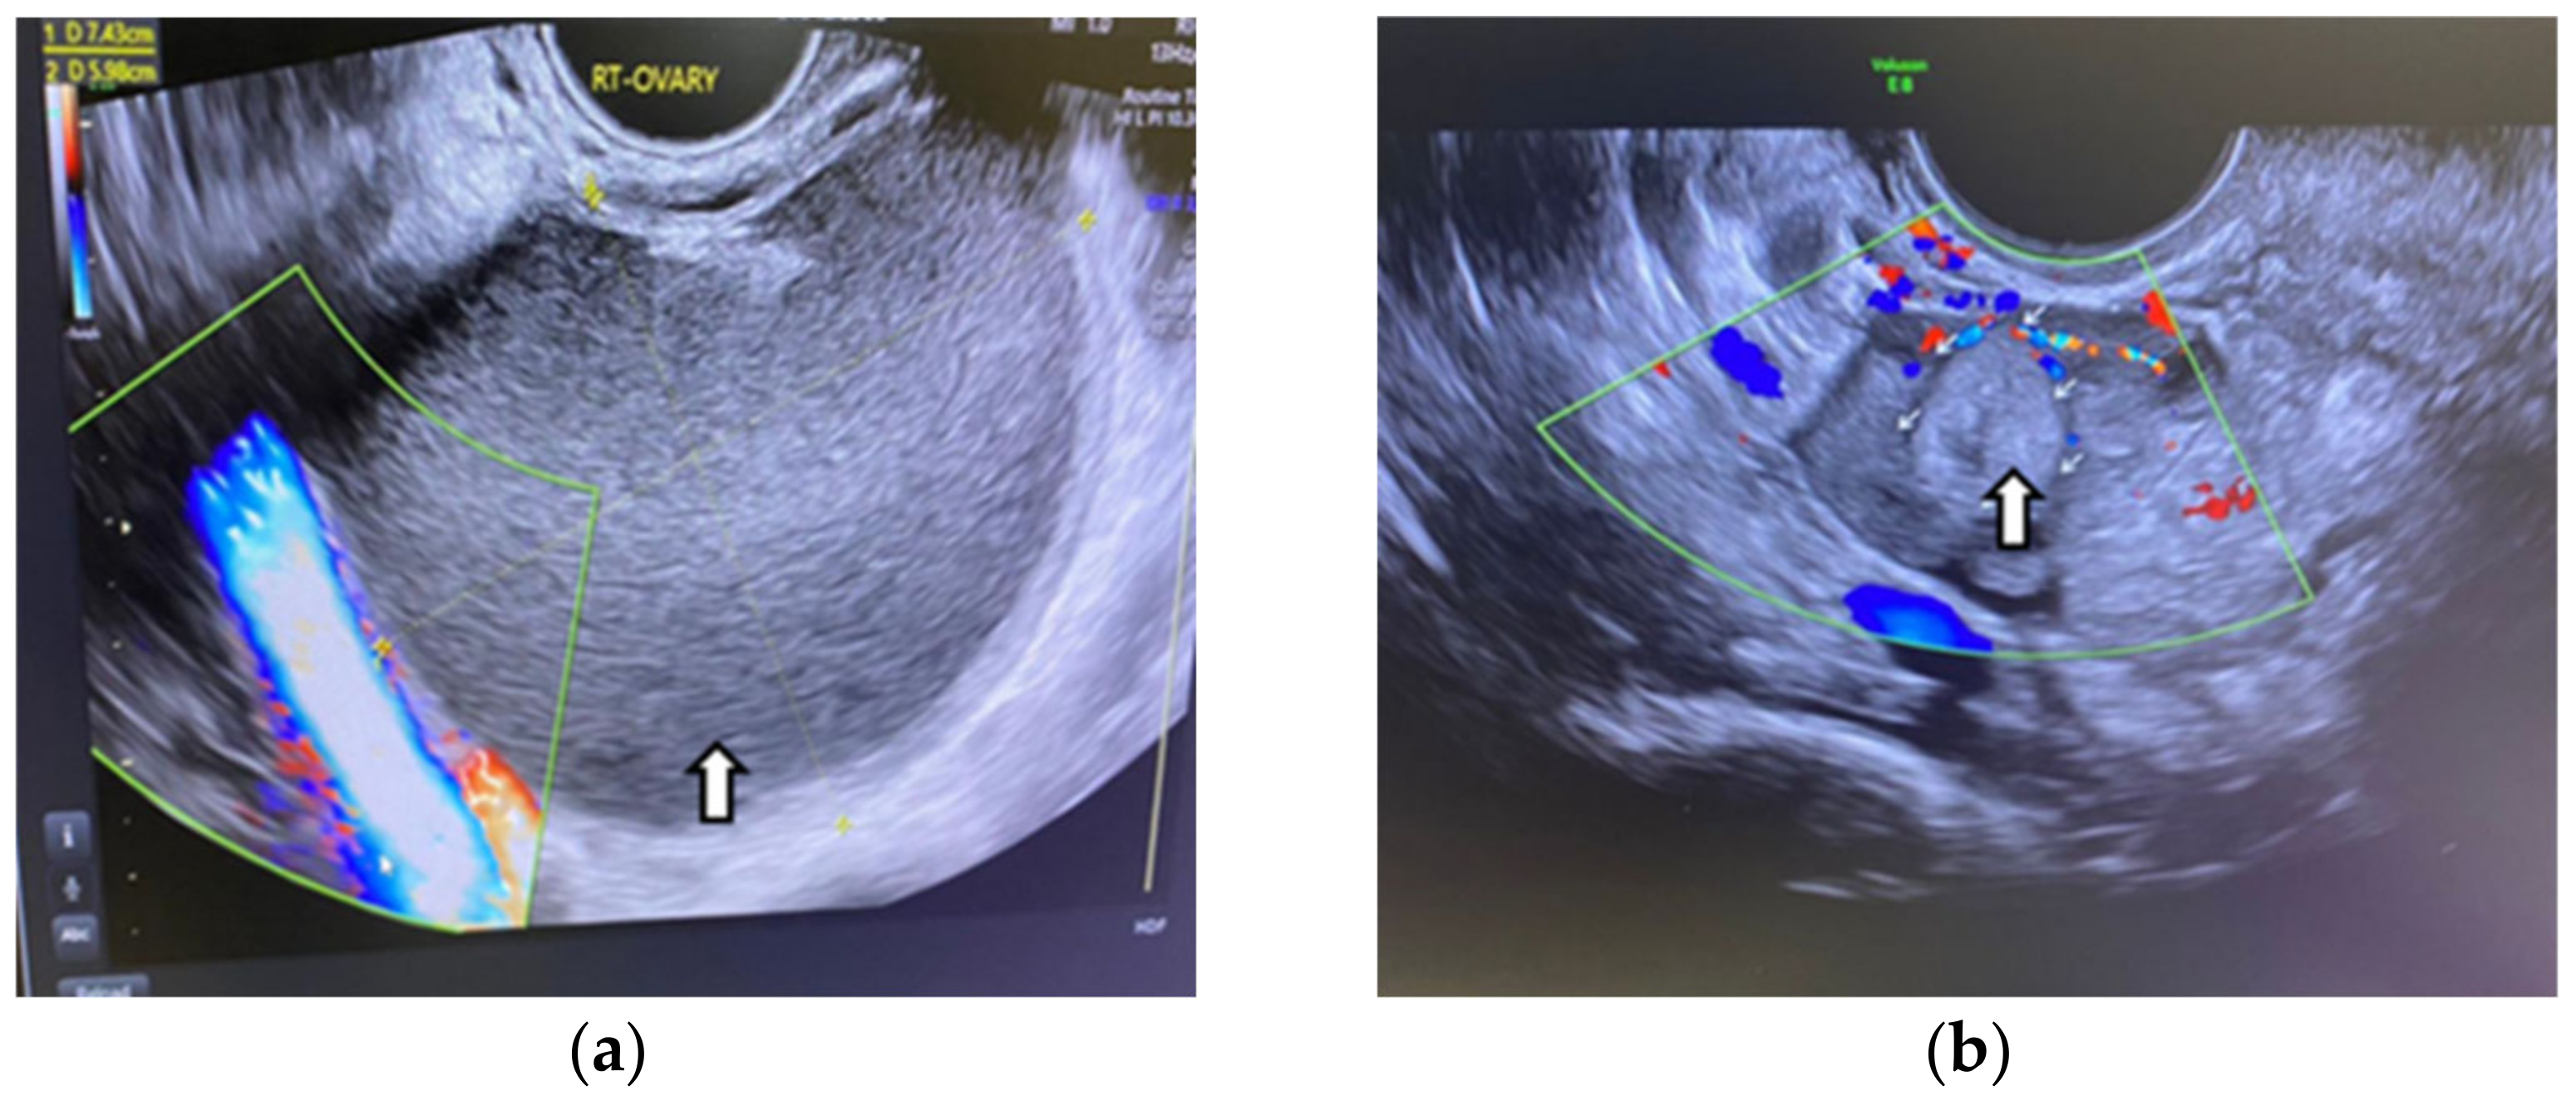

- Cohen Ben-Meir, L.; Mashiach, R.; Eisenberg, V.H. External Validation of the IOTA Classification in Women with Ovarian Masses Suspected to Be Endometrioma. J. Clin. Med. 2021, 10, 2971. [Google Scholar] [CrossRef] [PubMed] [PubMed Central]

- Guerriero, S.; Ajossa, S.; Gerada, M.; Virgilio, B.; Angioni, S.; Melis, G.B. Diagnostic value of transvaginal ’tenderness-guided’ ultrasonography for the prediction of location of deep endometriosis. Hum. Reprod. 2008, 23, 2452–2457. [Google Scholar] [CrossRef]

- Guerriero, S.; Alcazar, J.L.; Ajossa, S.; Pilloni, M.; Melis, G.B. Three-dimensional sonographic characteristics of deep endometriosis. J. Ultrasound Med. 2009, 28, 1061–1066. [Google Scholar] [CrossRef] [PubMed]